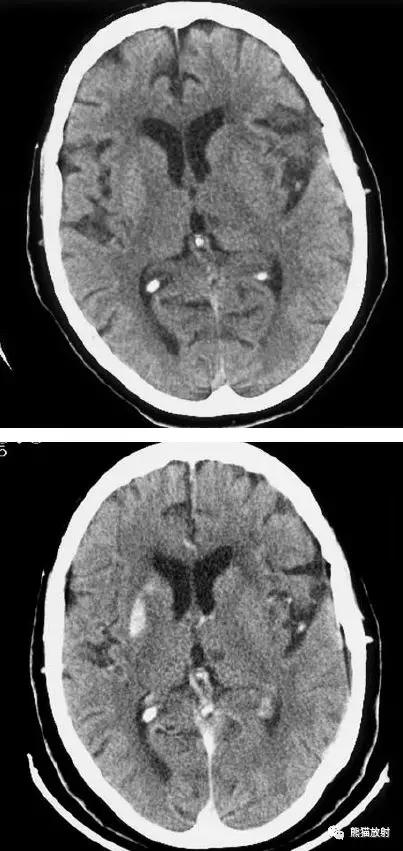

右侧基底节区脑梗死,增强后病灶看上去有所缩小。

出血性脑梗死

上矢状窦血栓形成,呈高密度(箭头);并邻近脑实质内出血性脑梗死。